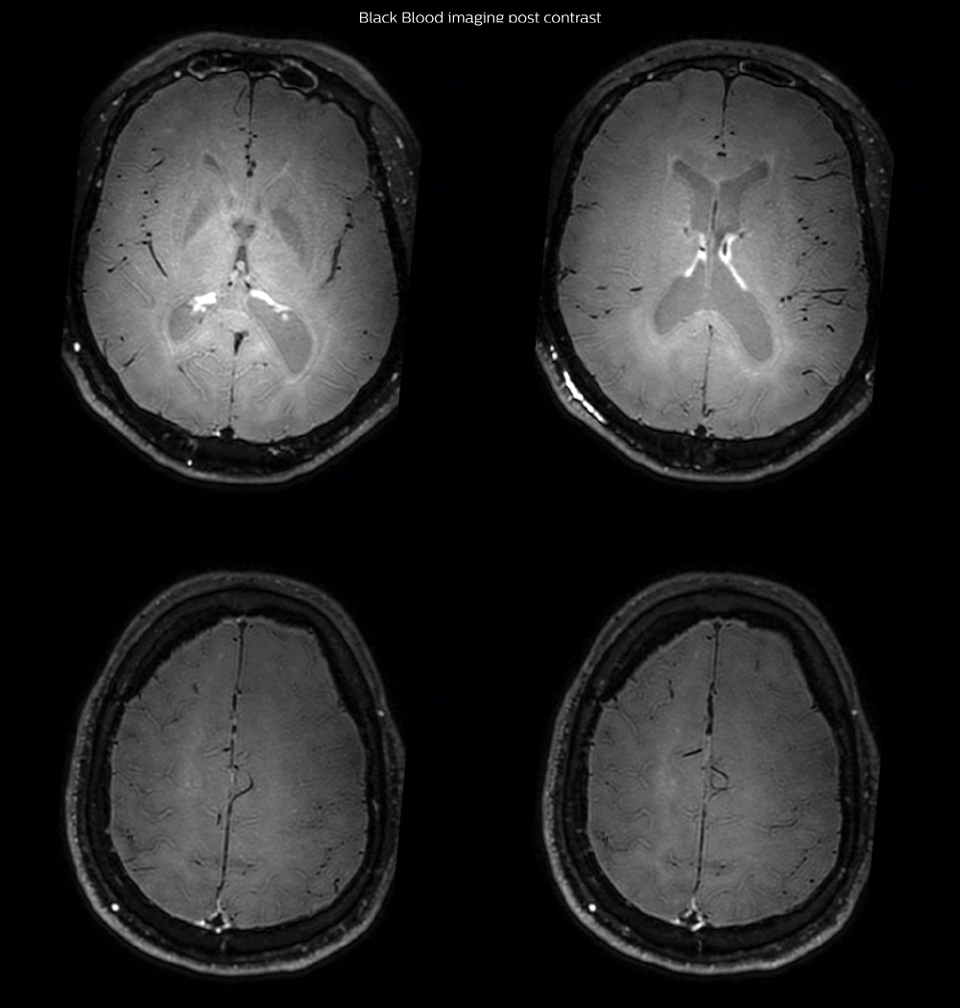

had, such as glucose intolerance, arterial hypertension and hypocholesteremia, his lesions could be atherosclerotic lesions or vasculitis, conditions which require different treatment. Especially in this patient with HIV infection causing the vasculitis, treatment of the two conditions is different. The results of MRI with Black Blood imaging, helped to choose the preferred treatment for this patient, which was based on antiviral medication rather than an antiaggregant or anticoagulation treatment which is usually given to patients with risk of ischemia based on atherosclerotic lesions. One month after beginning the antiviral treatment, the same MRI examination was repeated and again 8 months after the beginning of treatment. On follow-up images, we see the enhancements have almost disappeared. So in case of this patient, the MRI exam with Black Blood imaging helped us to give the patient the appropriate treatment and also allowed us to noninvasively confirm the treatment response.

With the multiple cardiovascular risk factors this patient

After one month of treatment, post-contrast Black Blood images at the exact same levels as in the figure above show disappearance of the vessel wall enhancements which were seen on the previous examination.